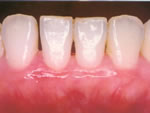

<治療前>

<治療後>